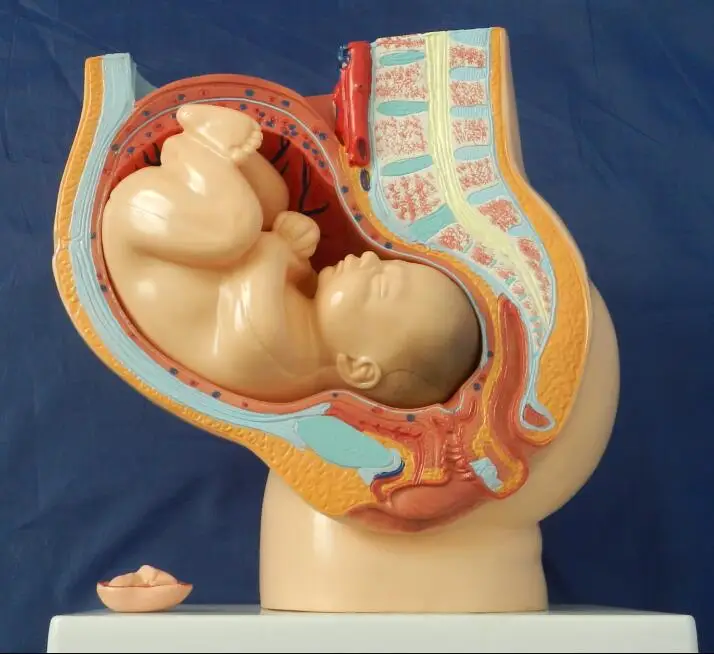

Анатомия малого таза: детальные схемы и изображения